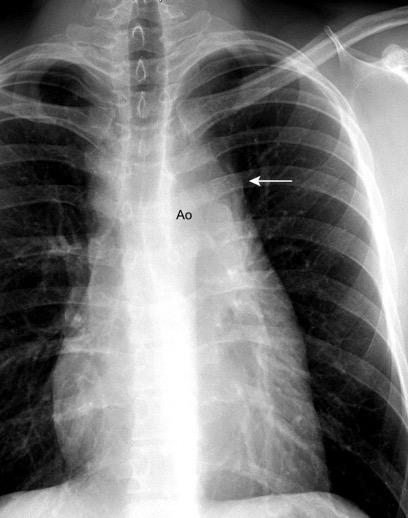

Visible en el adulto normal por interfase de la pared externa de la aorta con el aire del LII.

Causas de alteración

Normal

Patología aórtica Disección/ Aneurisma Úlcera ateroesclerótica

Adenopatías/ Ca. de Pulmón Hematoma Patología del LII

Marano R et al .Cardiac Silhouette Findings and Mediastinal Lines and Stripes. Chest 2011

30 años

Borramiento de la banda PARA-aórtica por AdenoCa. de LII, no visible en 2005

Colapso de LII. TC: secreciones bronquiales.

Endoscopia tapón mucopurulento extraído

Borramiento parcial por Ca. epidermoide.